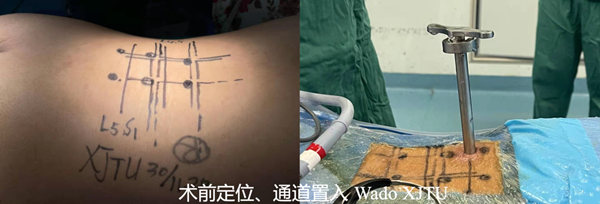

目前临床上针对此型病例,多采用传统的开放手术,即后方入路或椎间孔入路切开减压植骨融合内固定术(PLIF ,TLIF手术)。经治疗组认真讨论,考虑该患者较年轻,治疗组为该患者选择了脊柱内镜下的ENDO-TLIF/PLIF手术。应用脊椎内镜PLUS系统下的腰4/5,腰5/骶1椎间盘切除,椎管减压,植骨融合,经皮后路椎弓根螺钉内固定术,该术式属于内镜下微创手术,通过关节突及椎板的有限磨除,即可达到椎间盘切除及融合固定的手术目的,具有创伤小,早期恢复正常生活。此种术式难度较大,需要一定的脊柱内镜手术经验积累,目前国内仅有少数医院开展。